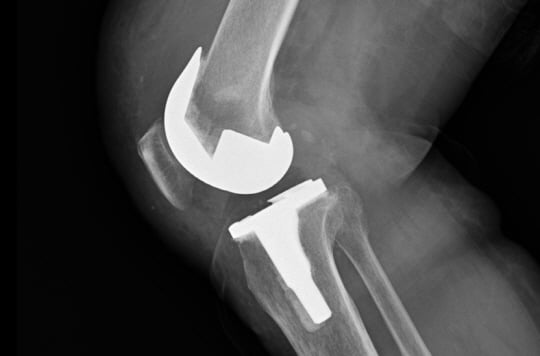

정재훈 안산 에이스병원 원장은 “무릎 인공관절 수술은 닳은 관절연골을 다듬고 금속으로 위아래 뼈를 감싸고 그 사이에 인공연골을 삽입하는 수술법이다. 수술 후 대부분 성공적인 결과를 99.5% 이상 보이지만 위험이 없는 수술은 아니다. 최근에 더 안전한 수술 방법이 시도되고 있다”고 밝혔다.

무릎 관절이 닳은 경우 약물이나 운동치료 혹은 주사치료 등 비수술 치료를 한 경우에도 불구하고 관절염 진행이 많이 되고 통증이 심한 경우 관절을 새로 치환하는 인공관절 수술을 하게 된다.